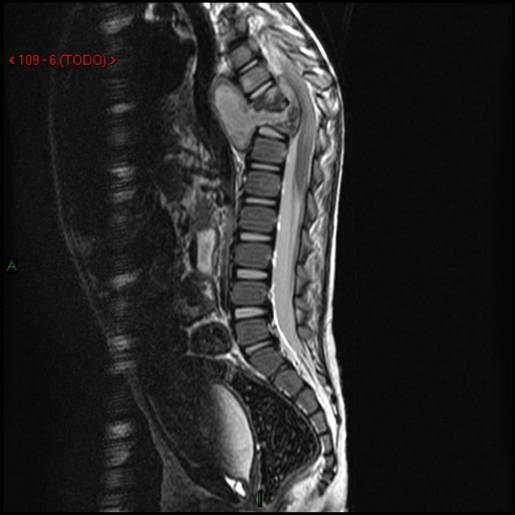

- Figura No 1a

- Figura No 1b

- Figura No 1c

- Figura No 1d

- Figura 1 Texto